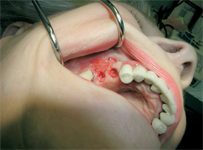

Novinkou v augmentačních metodách, kterou jako první v České republice používáme v našem zařízení je ultrazvuková metoda pomocí polylaktidové membrány - SonicWeld Rx®, kterou zavedl do implantologie v roce 2009 Dr. Dr. G.Iglhaut (Memmingen, Německo).

Jedná se o augmentační metodu při dostavbách kosti a defektech kosti horní a dolní čelisti.